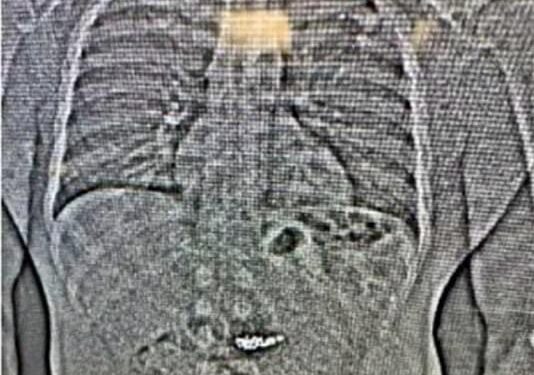

Poliția a localizat vehiculul lui Gilder pe Interstate 10 în drum spre Texas, iar bărbatul a fost reținut pentru opoziție la arestare. Inițial, nu au fost găsite bijuteriile asupra lui, iar Gilder nu a fost acuzat de furt. Cu toate acestea, în timpul arestării, autoritățile au efectuat o scanare corporală care a identificat „obiecte străine” în stomacul lui, despre care se crede că sunt cerceii furati.